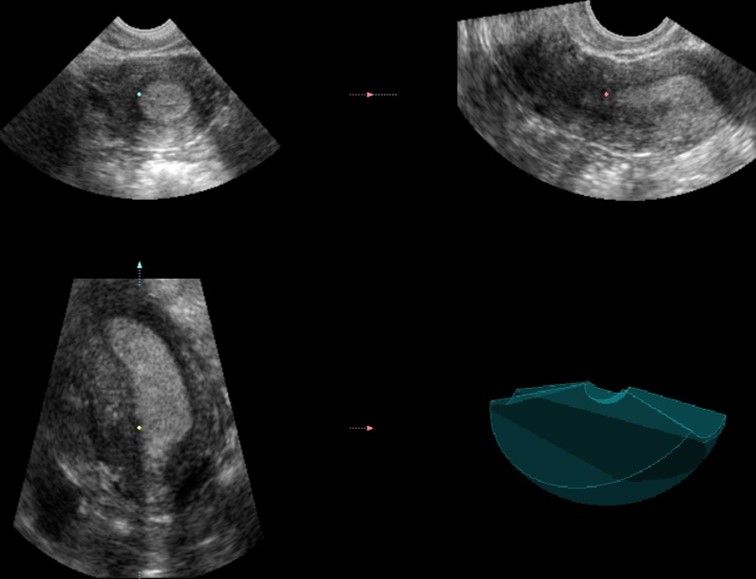

Современные экспертные УЗИ сканеры дают возможность проводить исследования всех органов в 3D. Это позволяет, используя полученный массив данных, получать диагностические сечения в любой плоскости, недоступной для обычного 2D УЗИ. Наиболее интересной является фронтальная. Например, визуализация полости матки. Диагностическая возможность выявления пороков развития превосходит все другие методы (рентгеновские и МРТ). Метод также позволяет уточнить положение ВМК (спирали) в полости матки, расположение миоматозных узлов, расположение плодного яйца на малых сроках, полипов. Сегодня современное экспертное ультразвуковое исследование невозможно без использования 3D УЗИ.